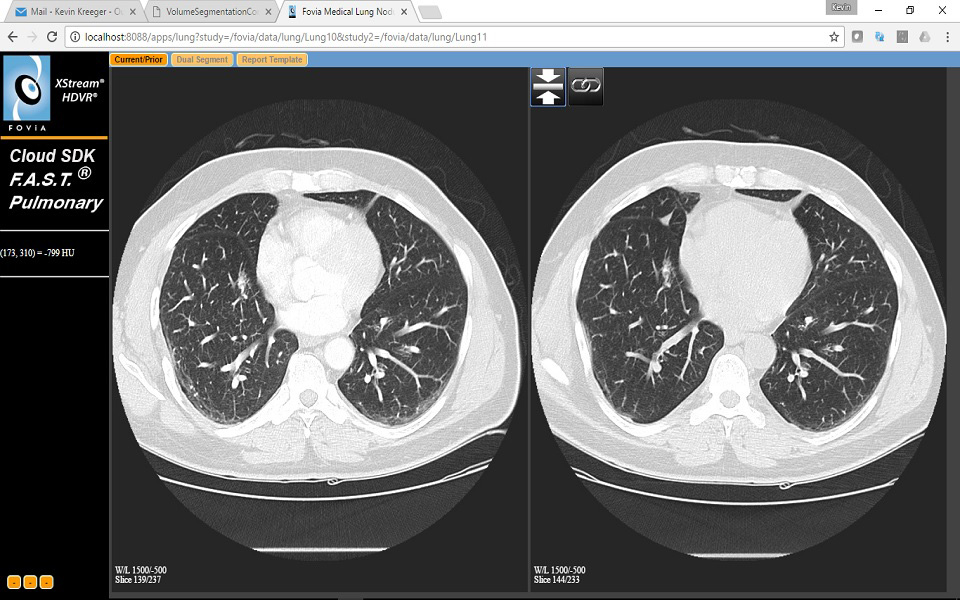

User Interface for Current Prior Lung App

The Current Prior Tab of the application consists of 2

viewports

Left – Current Axial image

Right – Prior Axial image

The images can be locked to scroll/pan/zoom synchronously.

The Dual Segment Tab is a 2x2 layout which matches the Nodule Segment

Tab from the first App but repeated for both the current and Prior

cases. And with the same controls.

The Current Prior Tab of the application consists of 2 viewports

- Left – Current Axial image

- Right – Prior Axial image

The images can be locked to scroll/pan/zoom synchronously.The Dual Segment Tab is a 2x2 layout which matches the Nodule Segment Tab from the first App but repeated for both the current and Prior cases. And with the same controls.